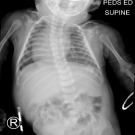

01/24/2019

VACTERL association is the presence of a minimum of 3 of 7 congenital abnormalities including vertebral, anal, cardiac, tracheoesophageal, renal, and limb abnormalities.